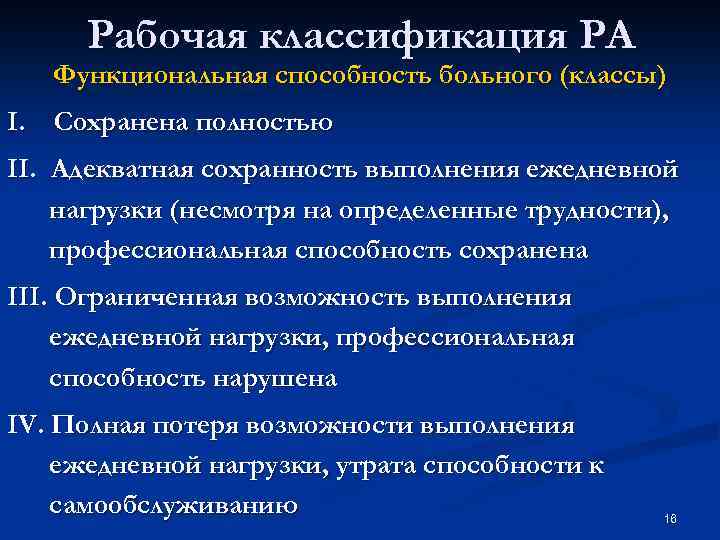

Рабочая классификация РА Функциональная способность больного (классы) I. Сохранена полностью II. Адекватная сохранность выполнения ежедневной нагрузки (несмотря на определенные трудности), профессиональная способность сохранена III. Ограниченная возможность выполнения ежедневной нагрузки, профессиональная способность нарушена IV. Полная потеря возможности выполнения ежедневной нагрузки, утрата способности к самообслуживанию 16

Рабочая классификация РА Функциональная способность больного (классы) I. Сохранена полностью II. Адекватная сохранность выполнения ежедневной нагрузки (несмотря на определенные трудности), профессиональная способность сохранена III. Ограниченная возможность выполнения ежедневной нагрузки, профессиональная способность нарушена IV. Полная потеря возможности выполнения ежедневной нагрузки, утрата способности к самообслуживанию 16